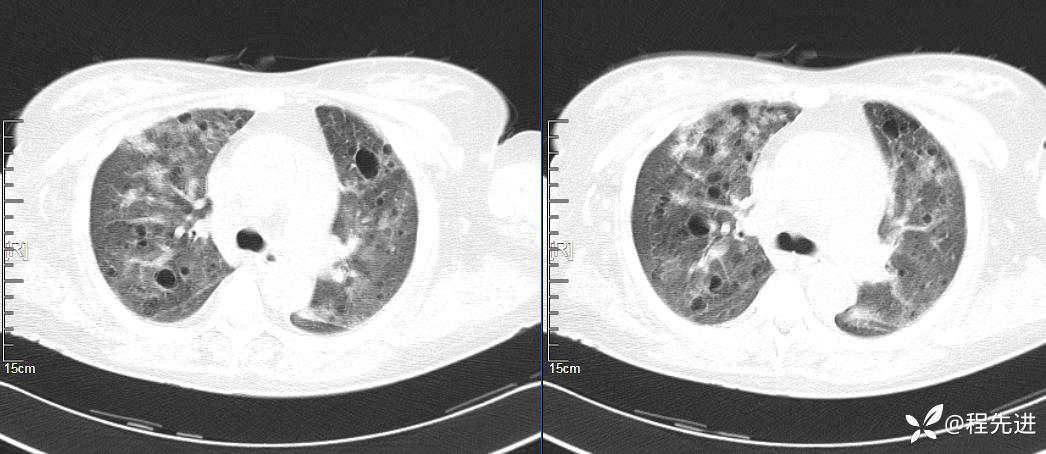

CT平扫(纵隔窗无特殊,就不上传了):

2、本例肺气囊分布有什么特点?肺气囊有无小叶核心?有没有间质纤维化及伴发结节?